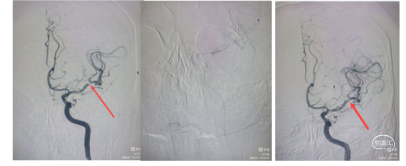

典型病例1: 静脉溶栓+机械碎栓治疗

病例简介:患者老年女性,76岁,“突发意识模糊,右侧肢体无力2小时”入院。查体左侧肢体肌力2级,心房颤动,NIHSS评分9分。CT无出血征象。急诊核磁DWI:左侧大脑半球高密度。

诊断:1.心源性栓塞可能;2.左侧大脑中动脉下干急性闭塞。

发病4.5小时内,NiHss评分9分,符合静脉溶栓,体重45kg。

静脉溶栓:给予阿替普酶37.8mg,首剂3.8mg团注,溶栓40分钟能言语,意识明显好转。肌力恢复不明显,牙龈少量出血。

机械碎栓+替罗非班:6Fguiging导引导管置于颈内动脉C1段起到支撑作用,微导丝到达M2段,微导管通过狭窄再回撤。撤出微导丝,微导管内推注替罗非班8ml (1ml/min),再次造影,血流明显改善。术后双联抗血小板聚集+阿托伐他汀、人尿激肽原酶--尤瑞克林治疗10天患者恢复良好,无明显后遗症。